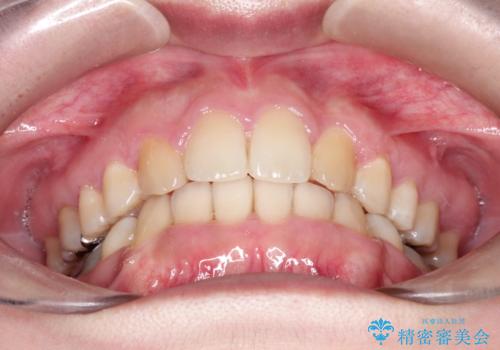

犬歯も通常の位置にまで移動することができ、口元もすっきりすることができました。